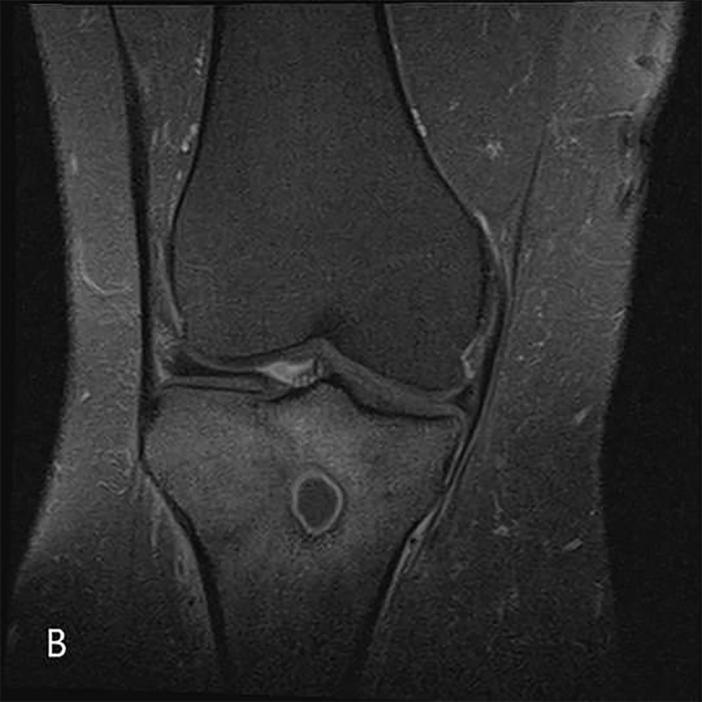

"Penumbra sign" of Brodie's abscess.